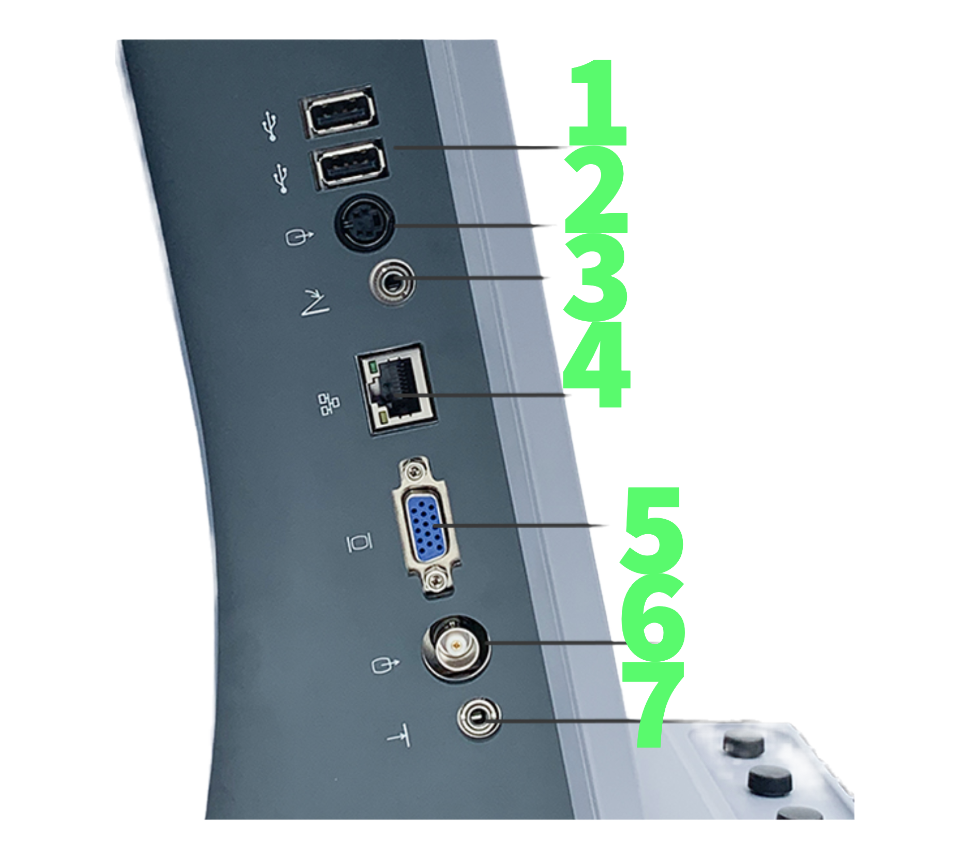

Боковая панель УЗИ аппарата U60

- USB Порт

- S-Video разъем

- Порт ножного переключателя

- Сетевое подключение

- VGA разъем

- Видеовыход

- Удаленный порт